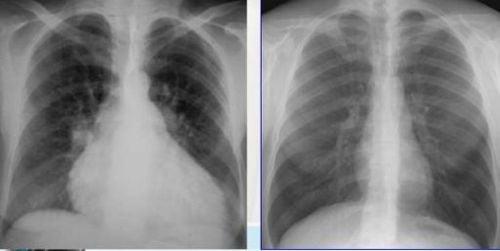

1. Bóng tim to

Để xác định bóng tim to trên phim chụp X-quang cần xác định tỷ lệ tim ngực, chỉ số tim ngực là tỷ lệ giữa kích thước chiều ngang của bóng tim và kích thước chiều ngang lồng ngực. Bóng tim bình thường trên phim chụp tim phổi thẳng có tỷ lệ tim ngực là từ 0,5-0,55. Bóng tim to khi tỷ lệ tim ngực lớn hơn 0,55.

Nguyên nhân gây ra hiện tượng bóng tim to trên phim chụp bao gồm:

• Suy tim: Suy tim có thể do nhiều nguyên nhân gây ra, khi có tình trạng suy tim các tế bào cơ tim phải tăng sức làm việc, dẫn đến cơ tim bị phì đại, máu bị ứ lại trong buồng tim và tạo thành hình ảnh bóng tim to trên phim chụp X-quang.

• Bệnh lý van tim: Một bất thường hệ thống van tim như: Hẹp hở van hai lá, van 3 lá hay van động mạch chủ... Cũng làm cho máu bị ứ lại trong buồng tim gây ra hiện tượng bóng tim lớn trên phim.

• Tràn dịch màng ngoài tim: Tràn dịch màng ngoài tim là nguyên nhân gây hiện tượng khó thở, đau ngực trên lâm sàng. Tràn dịch màng ngoài tim là hiện tượng dịch giữa khoang màng ngoài tim tăng lên một cách bất thường, dẫn đến chèn ép tim. Hiện tượng dịch tăng ở màng ngoài tim bất thường cũng làm thay đổi hình ảnh bóng tim trên phim chụp X-quang.

• Bệnh lý tim bẩm sinh như: Từ chứng fallot ( thấy tim hình giống chiếc ủng), bệnh Ebstein( tim có hình giống hình hộp)...

Hình ảnh bóng tim to trên X quang